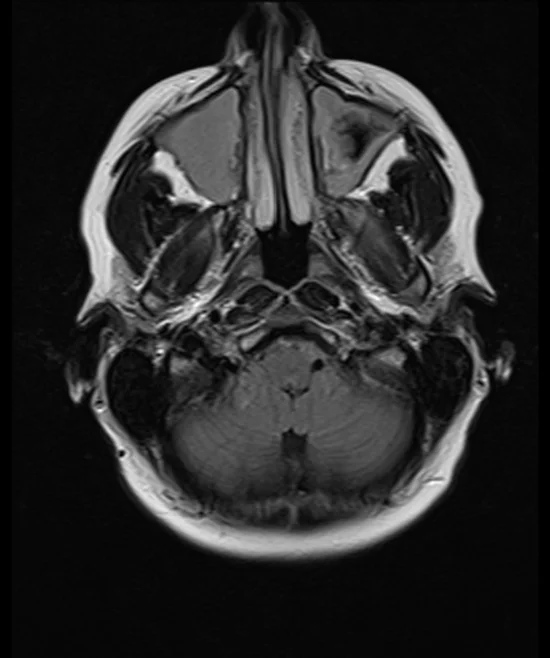

brain mri t2 flair axial images